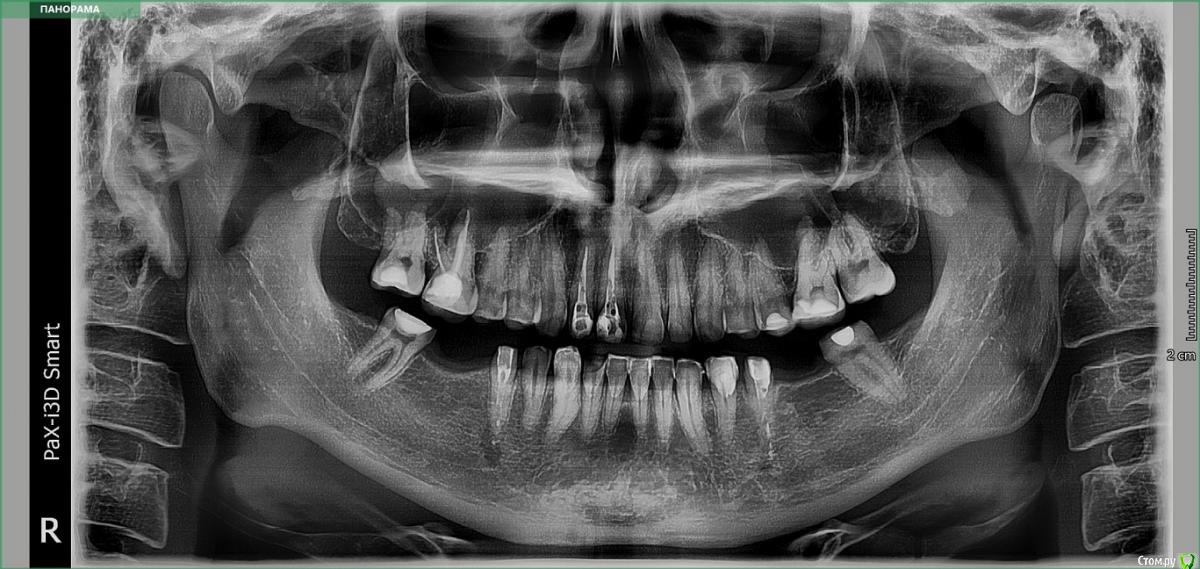

Подскажите пожалуйста, не видно ли периодонтита по снимку - два 5 нижних зуба? 1,2 сверху хорошо каналы запломбированы? Ставили 4 стекловолоконных штифта, готовим нижние зубы для установки двух мостов из диоксида циркония по бокам, на 8 нижних и 10 верхних - керамические виниры. На данный момент беспокоит ноющая боль на 4 или 5 нижнем зубе слева. Первый снимок - до обточки зубов, второй - после обточки и установки штифтов.